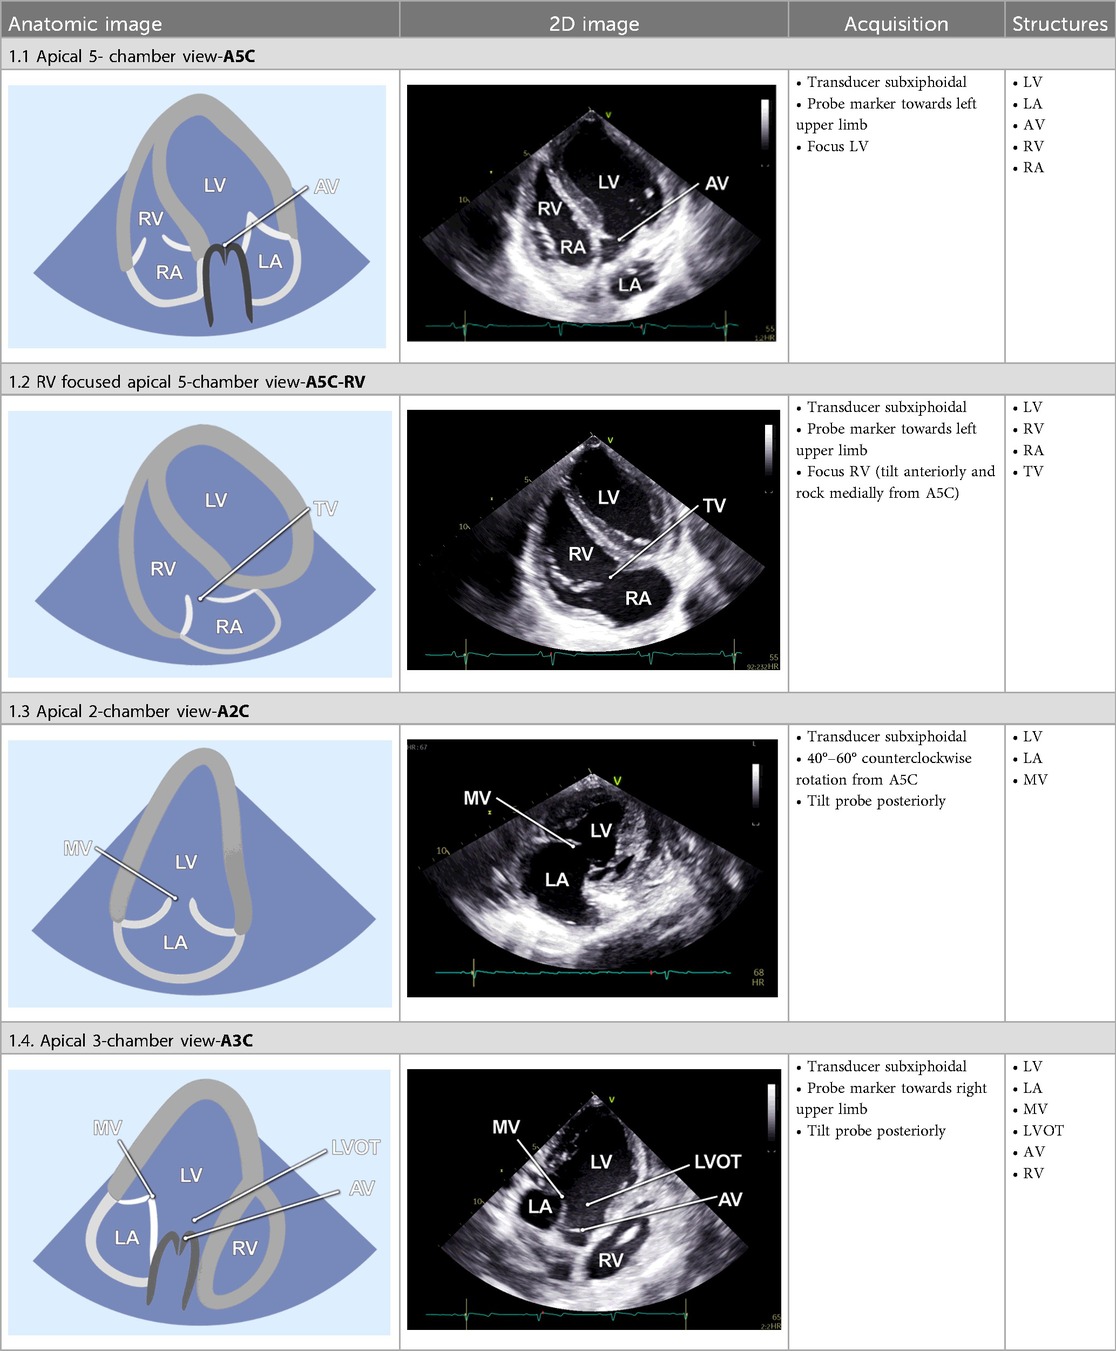

Table 1

www.frontiersin.org

Table 1. Standard two-dimensional imaging protocol for swine.

2.2.2 Apical 5-chamber view

The examination started with an apical 5-chamber (A5C) view. The ultrasound transducer was therefore placed subdiaphragmatically, with the probe marker oriented laterally to the left (90°–110°) and tilting slightly anteriorly (10°–20°). Due to the anatomical configuration of the swine heart, a standardized 4-chamber view is rarely obtainable. Instead, the long axis of the porcine heart extends obliquely from right to left and from posterior to anterior. This modified view allowed for clear visualization of both ventricles, although the atria could be only partially visualized (Table 1). Importantly, the left ventricular outflow tract (LVOT), the aortic valve (AV) and root can be adequately visualized in a manner analogous to a human 5-chamber view. To enhance the echocardiographic evaluation, lateral or medial adjustments of the focus improved the visualization of both ventricles, facilitating volumetric measurements and speckle-tracking analysis. Additionally, proper alignment of the Doppler beam enabled valid Doppler echocardiographic assessment of the AV and the LVOT (Figure 3).

2.2.3 RV-focused apical 5-chamber view

In the RV-focused apical 5-chamber view (A5C-RV), the transducer was tilted anteriorly and rocked medially to optimize the visualization of the RV (Table 1). The view focuses on the RV and the tricuspid valve (TV) with partial visualization of the LV. This view was used for detailed evaluation of RV anatomy and function, including the RV free wall longitudinal strain, right ventricular basal diameter, tricuspid annular plane systolic excursion (TAPSE), and tricuspid annular systolic velocity (TASV) (Figure 3). In addition, the tricuspid valve (TV) could be assessed by Doppler echocardiography in this view.

2.2.4 Apical 2-chamber view

The 2-chamber view (A2C) was obtained by rotating the transducer counterclockwise by 40°–60° from the A5C view and tilting it posteriorly. This view visualizes the LV (including the inferior and anterior wall), the mitral valve (MV) and the left atrium (LA) (Table 1). It is essential for the assessment of LV function and MV motion. Measurements of LV end-diastolic volume (LVEDV), LV end-systolic volume (LVESV), LV- global longitudinal strain (LV-GLS), Pulsed-wave (PW) Doppler and continuous-wave (CW) Doppler of the MV could be conducted in this view. Image acquisition in this view was sometimes challenging when the RV was poorly filled.

2.2.5 Apical 3-chamber view

Further counterclockwise rotation of the transducer (50°–60°) and slight posterior tilting from the A2C were required to obtain the 3-chamber view (A3C). This view displays the LV (inferolateral and anteroseptal walls), the LVOT, the AV, and the MV (Table 1). It is particularly useful for imaging aortic structures and LV anatomy, allowing for the assessment of LV-GLS, as well as PW and CW Doppler of the AV.